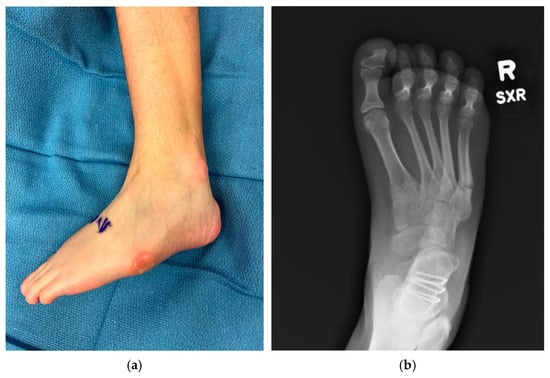

Cerebral palsy (CP) is a developmental disability caused by injury to the fetal or infant brain, affecting between 1.6 to 3.7 per 1000 live births worldwide. Ambulatory patients with cerebral palsy experience various gait problems, for which they seek treatment from medical professionals. Varus foot deformities are among the most problematic for patients. Varus foot deformity is characterized by the inner border of the foot being tilted upward and the hindfoot inward, increasing weightbearing on the lateral aspect of the foot. This positioning increases weight-bearing pressure under the lateral (outside) of the foot and often under the fifth metatarsal head when walking. As such, varus foot deformity can contribute to in-toeing, make shoe and brace-wearing difficult and painful, compromise gait stability, and sometimes lead to metatarsal fractures. Current knowledge of CP etiology and classifications, as well as principles and advances in assessment and treatment decision making for varus foot deformities, are outlined in this narrative review. In younger children with flexible deformities, non-operative interventions such as bracing, botulinum toxin injection, and serial casting are effective. The literature and expert consensus suggest that, if possible, surgery should be delayed until after the age of 8 years. When surgery is indicated, soft tissue procedures are used for flexible deformities. In addition to the soft tissue procedures, bone surgery is needed for rigid deformities. Careful pre-operative foot assessment is needed, including assessment of deformity flexibility and range of motion, X-rays, and computerized gait analysis if possible. Strategies are presented for thorough assessment when gait analysis is not available or feasible. Research reports of surgical outcomes for soft tissue and bony correction are positive, but should be interpreted with caution. The quality of evidence on surgical outcomes is compromised by use of varying research design methods and selection of outcome measures, with few including measures of function or patient-reported outcomes. It is recommended that surgical outcome be assessed using standardized assessment tools, such as the Foot Posture Index, which have had their validity and reliability established. Recent advances in 3D kinematic foot model development and musculoskeletal modeling have the potential to greatly improve surgical outcomes for patients with CP. Full article

Show Figures

Figure 1